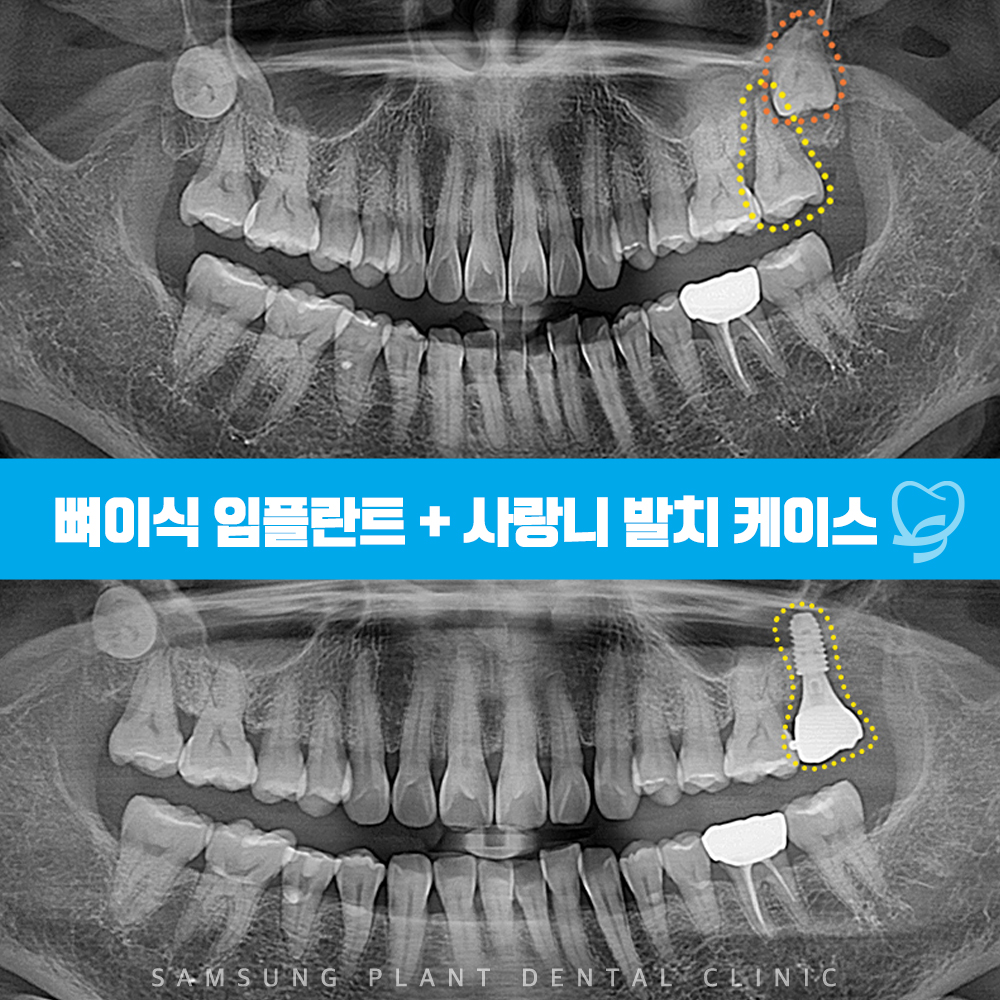

파노라마 사진을 촬영해 체크해보니

불편을 호소하는

노란색 표시의 어금니는

잇몸뼈가 녹고 염증소견도 관찰되었습니다.

또한 매복된 사랑니(주황색 표시)도

확인할 수 있었답니다.

신정네거리치과

전체적으로 스케일링을 시행하고

두번째 어금니와 사랑니를

깔끔하게 발치해준 모습입니다.

발치 후에는

추후 임플란트 수술을 진행할 수 있도록

자가혈청을 이용한 뼈이식을 진행했습니다.

발치 및 뼈이식을 진행하고

4개월의 충분한 회복 기간을 거친 뒤

임플란트 수술을 진행한 모습입니다.